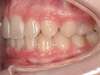

Cas 4 : Description

Chevauchement sévère. Traitement multibague sans extraction.

Avant

Après